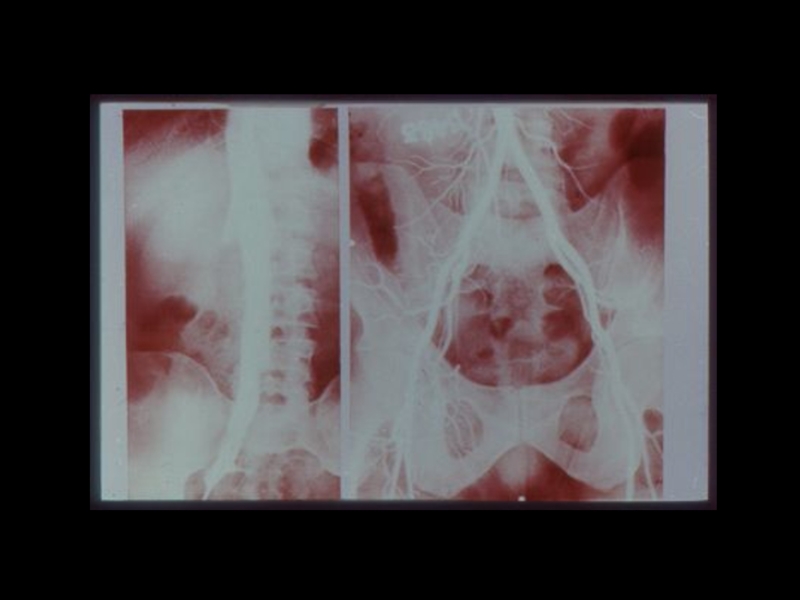

Слайд 39Йодсодержащие рентгеноконтрастные вещества:

I. Ионные - трийодзамещенные

1) Водные (

урографин, уротраст, верографин,

йодамид, триомбраст )

2) Масляные ( Йодолипол, майодил, лимфотраст)

II.Неионные ( 1974 )

1) Циклические трийодзамещенные неионные

мономеры ( Амнипак, омнипак, имагопак)

2) Неионные гексайодированные димеры

( молекула состоит из 2-х бензольных колец с

атомами йода)

- Везипак ( для ангиографии)

- Иотролан ( для миелографии )

Йодсодержащие рентгеноконтрастные вещества:I. Ионные - трийодзамещенные  1) Водные ( урографин, уротраст, верографин,